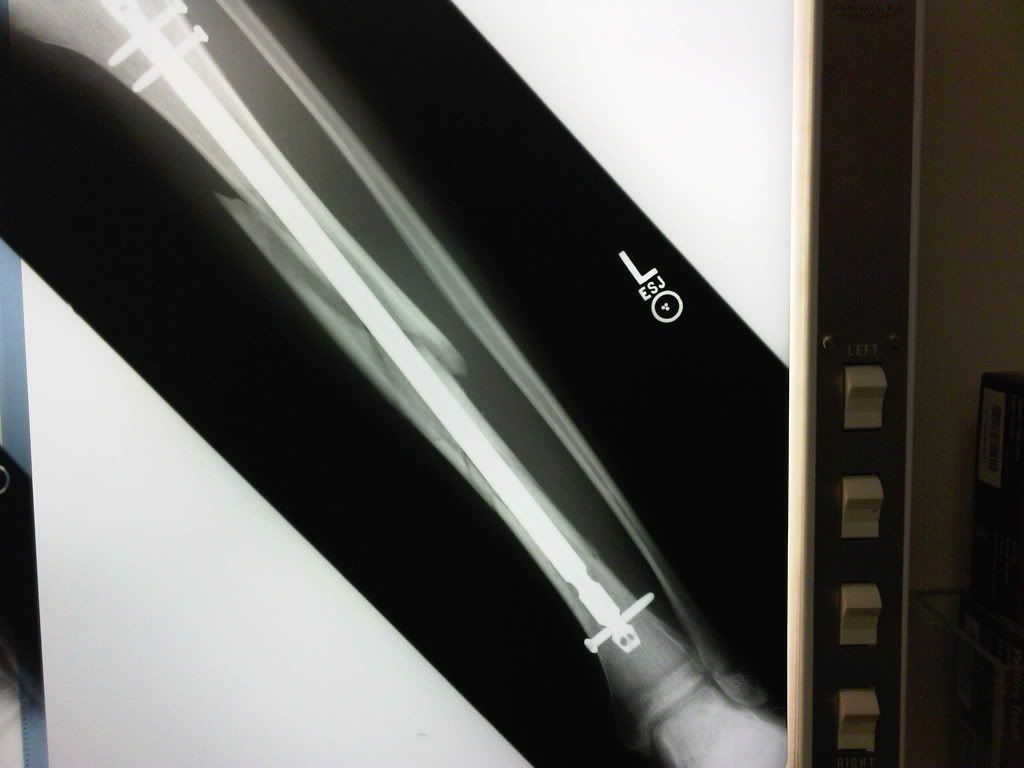

hey guys looks like martini and i are in the same boat skiing wise instead of tearin up my knee though i broke my tibia in 27 places. I was night skiing mobbin around and ended up goin off this 7-12 foot routine burm/cliff thing but had too much speed. my right ski ejected and my left one didn't, i ended up sliding down the run for a good 40 yards after the "landing" with my right ski ragdolling and not ejecting just twisting the bones and muscles. Heres the X-ray. I've already gone in for 3 surgeries and they put in a rod and 4 screws, made two open wounds up the sides of my leg so swelling doesn't kill my muscle and reset it. I have one more surgery this afternoon to seal up those open wounds. No more skiing this season, no more competitions but ill be shooting/filming alot hopefully.